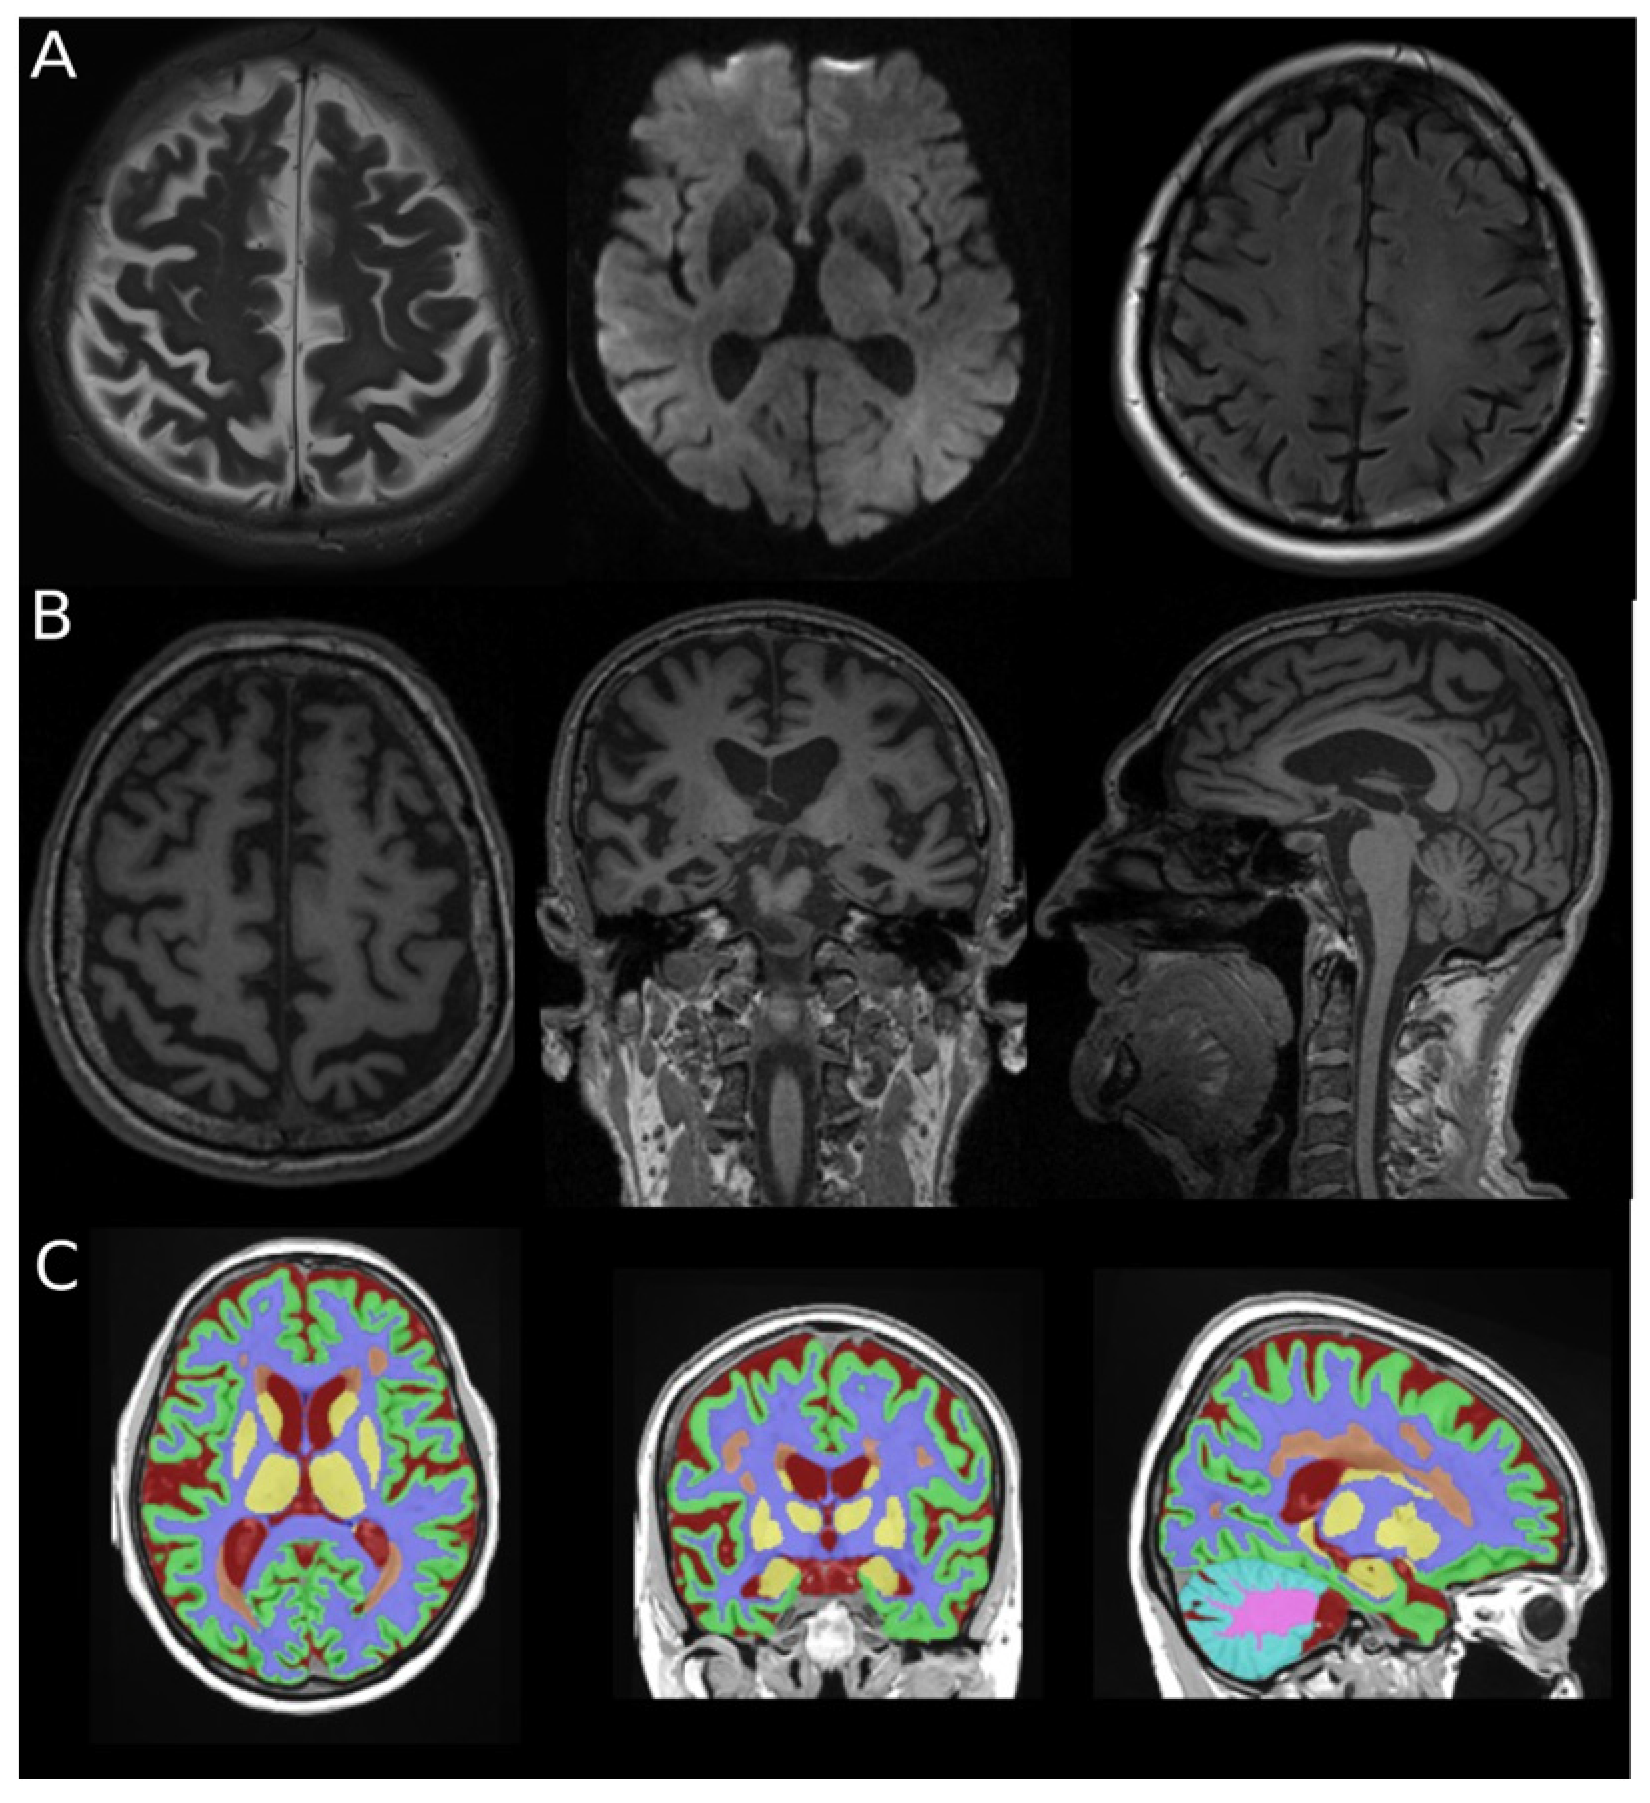

2.3. MRI Acquisition and Volumetric Analysis